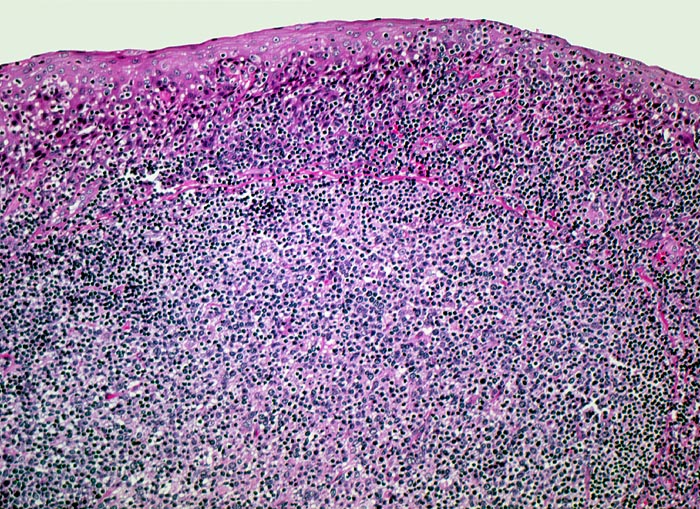

Lymphknoten, lymphatisches Gewebe des Oropharynx und Tonsillen zeigen ähnliche Veränderungen:

• Aktivierung der B-Lymphozyten-Areale (EBV induzierte polyklonale Infektion und Stimulation der EBV-Rezeptor tragenden B-Zellen): grosse, aktivierte Keimzentren (=follikuläre Hyperplasie), aktive parafollikuläre Plasmazellbildung (B-Immunoblasten, Plasmoblasten, Plasmazellen).

• Aktivierung der interfollikulären T-Zone (= sogenannte bunte Pulpahyperplasie) mit Hodgkin-artigen Zellen (= reaktive/aktivierte B- resp. T-Lymphozyten).

• Interfollikuläre Hyperplasie der T-Zone (bunte Pulpahyperplasie):

Hodgkinartige Zellen (=reaktive/aktivierte B- resp. T-Lymphozyten), kleine Lymphozyten, Immunoblasten mit zentralem Nukleolus und Plasmazellen.